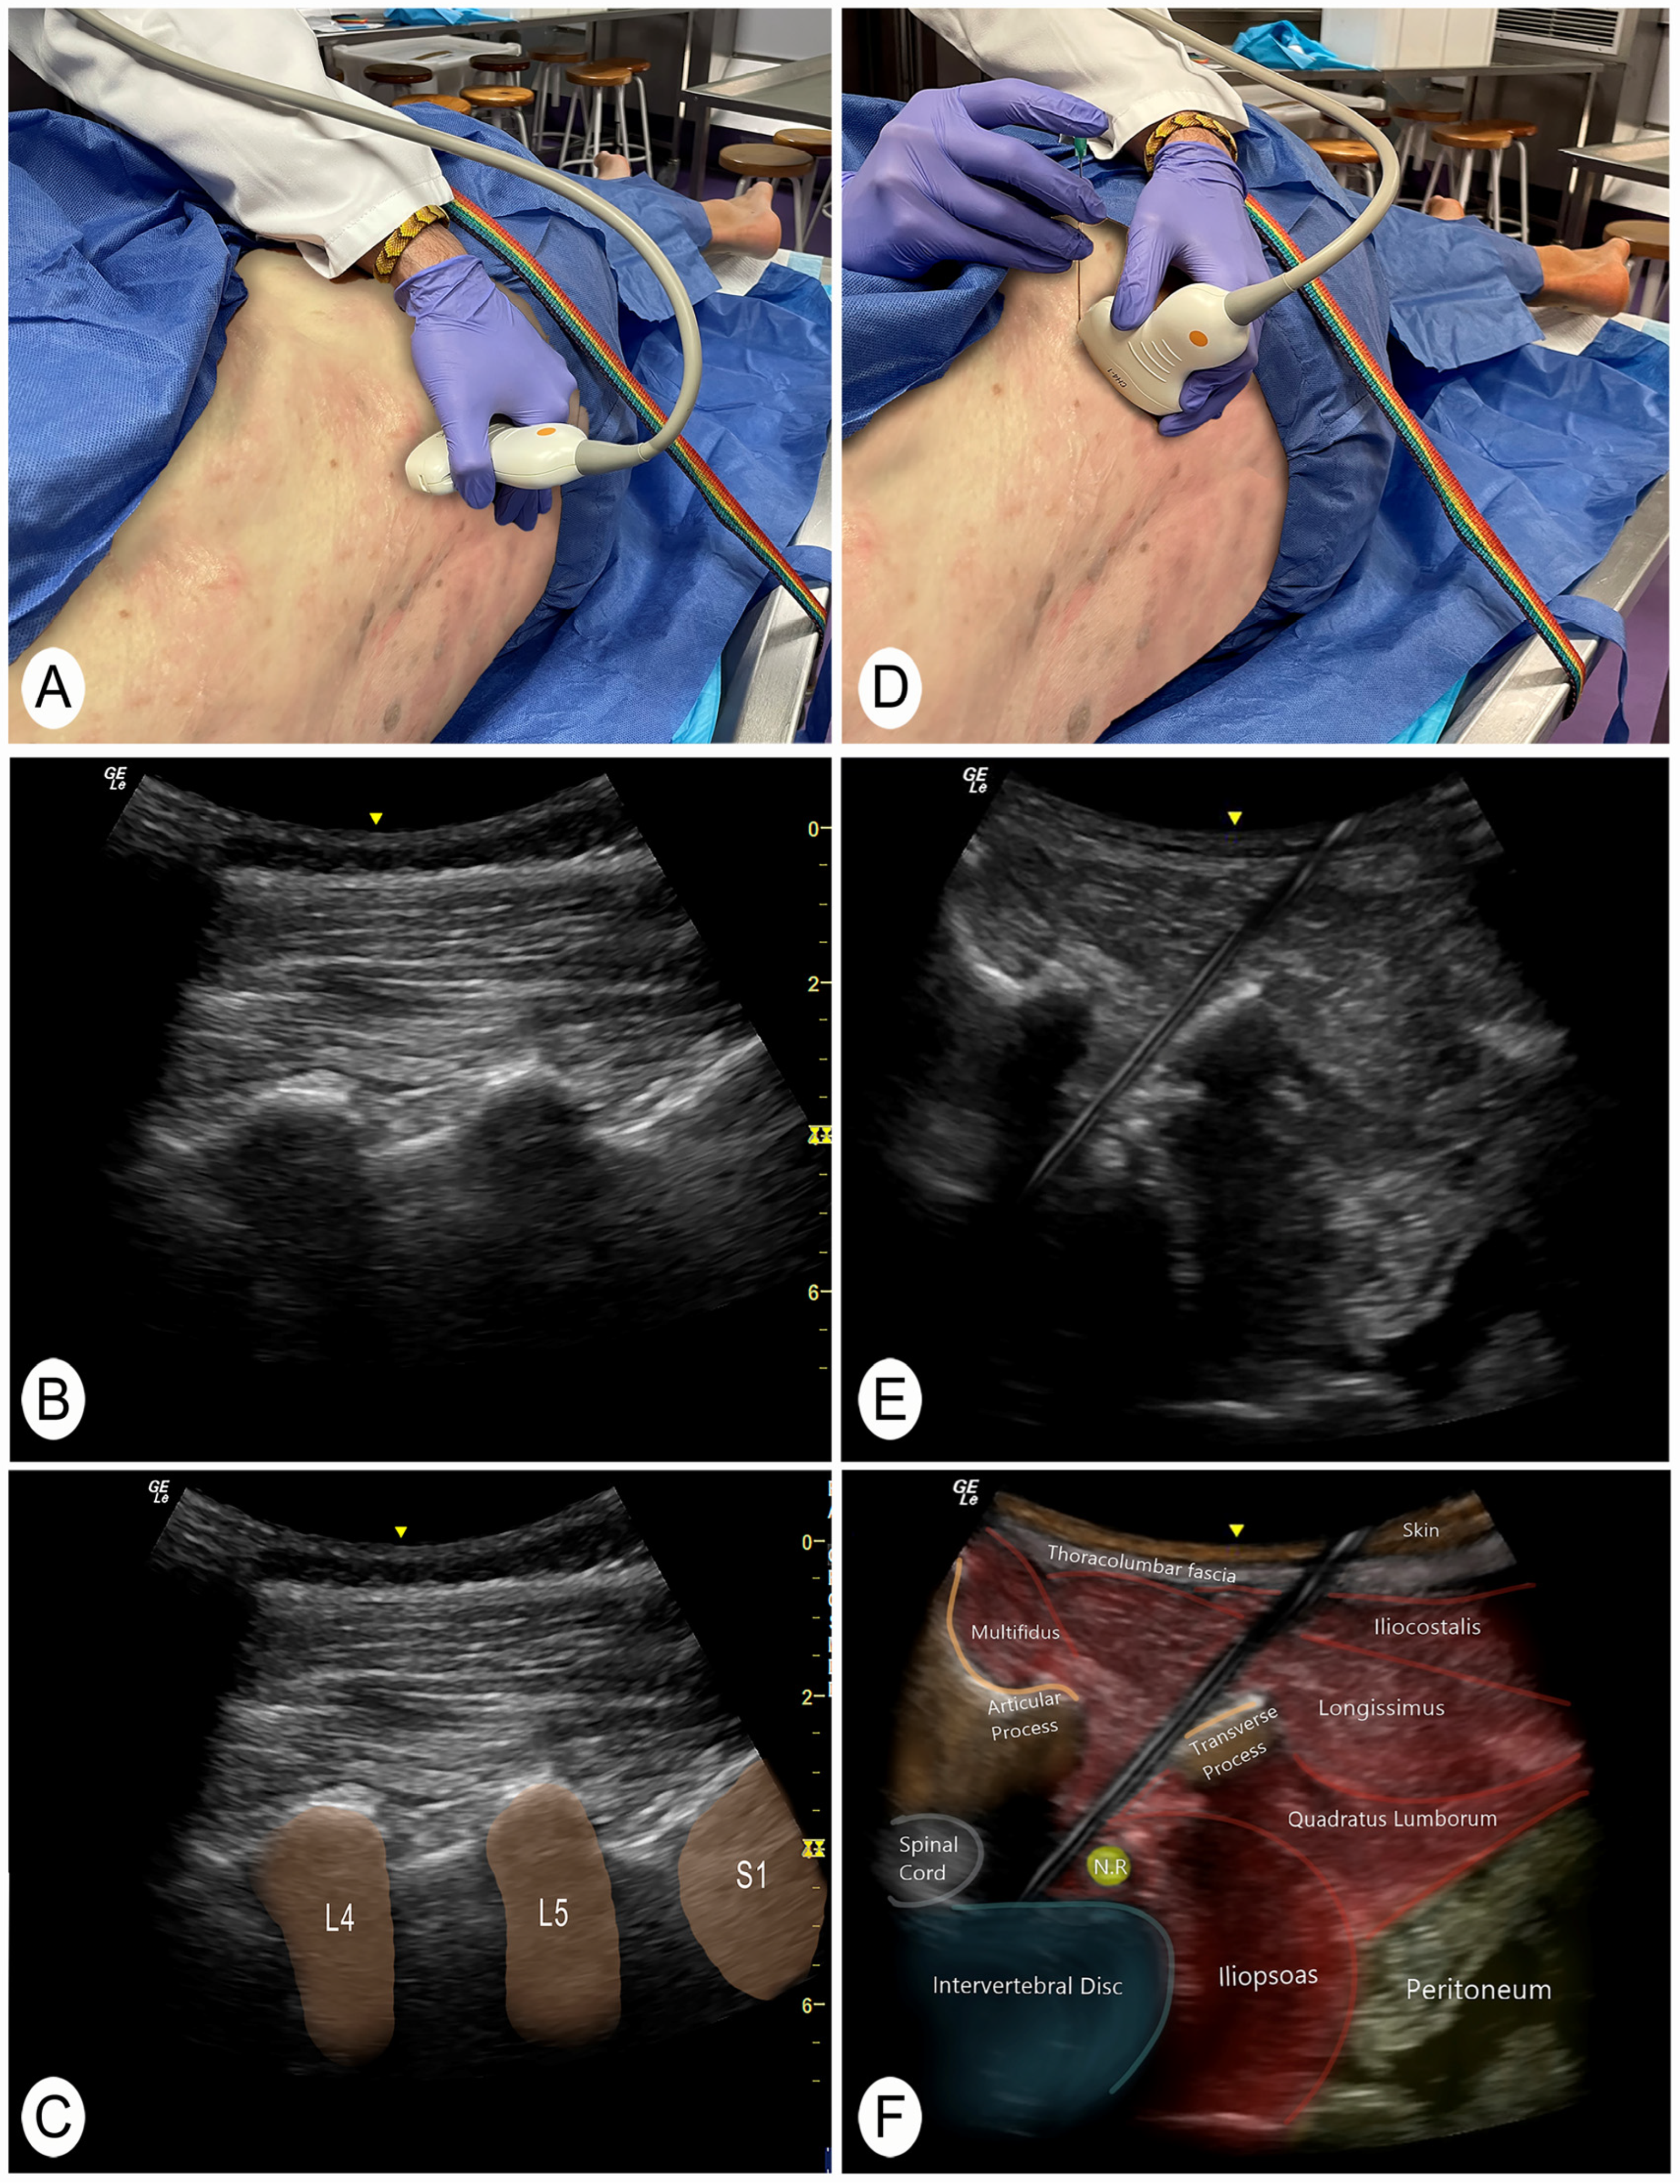

A posterior to anterior and lateral to medial approach was performed with the cadaver in lateral decubitus. To identify the target intervertebral segment, the sacrum was located manually. The transducer was then placed in a longitudinal plane of the spine to locate the facet joints (Figure 1A–C) [22]. With this image, the sacral bone and the intervertebral spaces could be clearly identified. This technique for identifying vertebral segments has been shown to be effective in the previous literature [22]. The target intervertebral space was then placed in the center of the screen and a cross-section was made with the ultrasound transducer. In this section, the spinous process, the lamina, the articular facet, and the anterior nerve root of the targeted segment were visualized [5]. The transducer was then moved slightly laterally until a clear image of the anterior root and intervertebral disc was obtained. In addition, an obliquity was generated with the lateral part of the transducer to avoid the transverse processes of the vertebrae. In the case of L5, the lateral end of the ultrasound transducer was moved slightly in a cranial direction to avoid the iliac bone. The needle was then introduced until it reached the posterolateral part of the intervertebral lumbar disc (Figure 1D–F and Figure 2A,B).

Figure 1.

Posterior and lateral ultrasound of the invasive technique. Abbreviations: N.R., nerve root. L4, 4th lumbar vertebra; L5, 5th lumbar vertebra; S1, 1st sacral vertebra. (A) Position to locate the vertebral level with the transducer in a longitudinal slice of the facet joints. (B) Ultrasound image of the longitudinal section of the lumbar articular facets. (C) Ultrasound image of the longitudinal section of the lumbar articular facets with the vertebral segments identified. (D) Position of the transducer to perform the invasive technique in a posterolateral transverse section of the intervertebral disc. (E) Cross-sectional ultrasound image from a posterolateral view where the invasive technique of the intervertebral disc is performed. (F) Ultrasound cross-sectional identification of the structures.